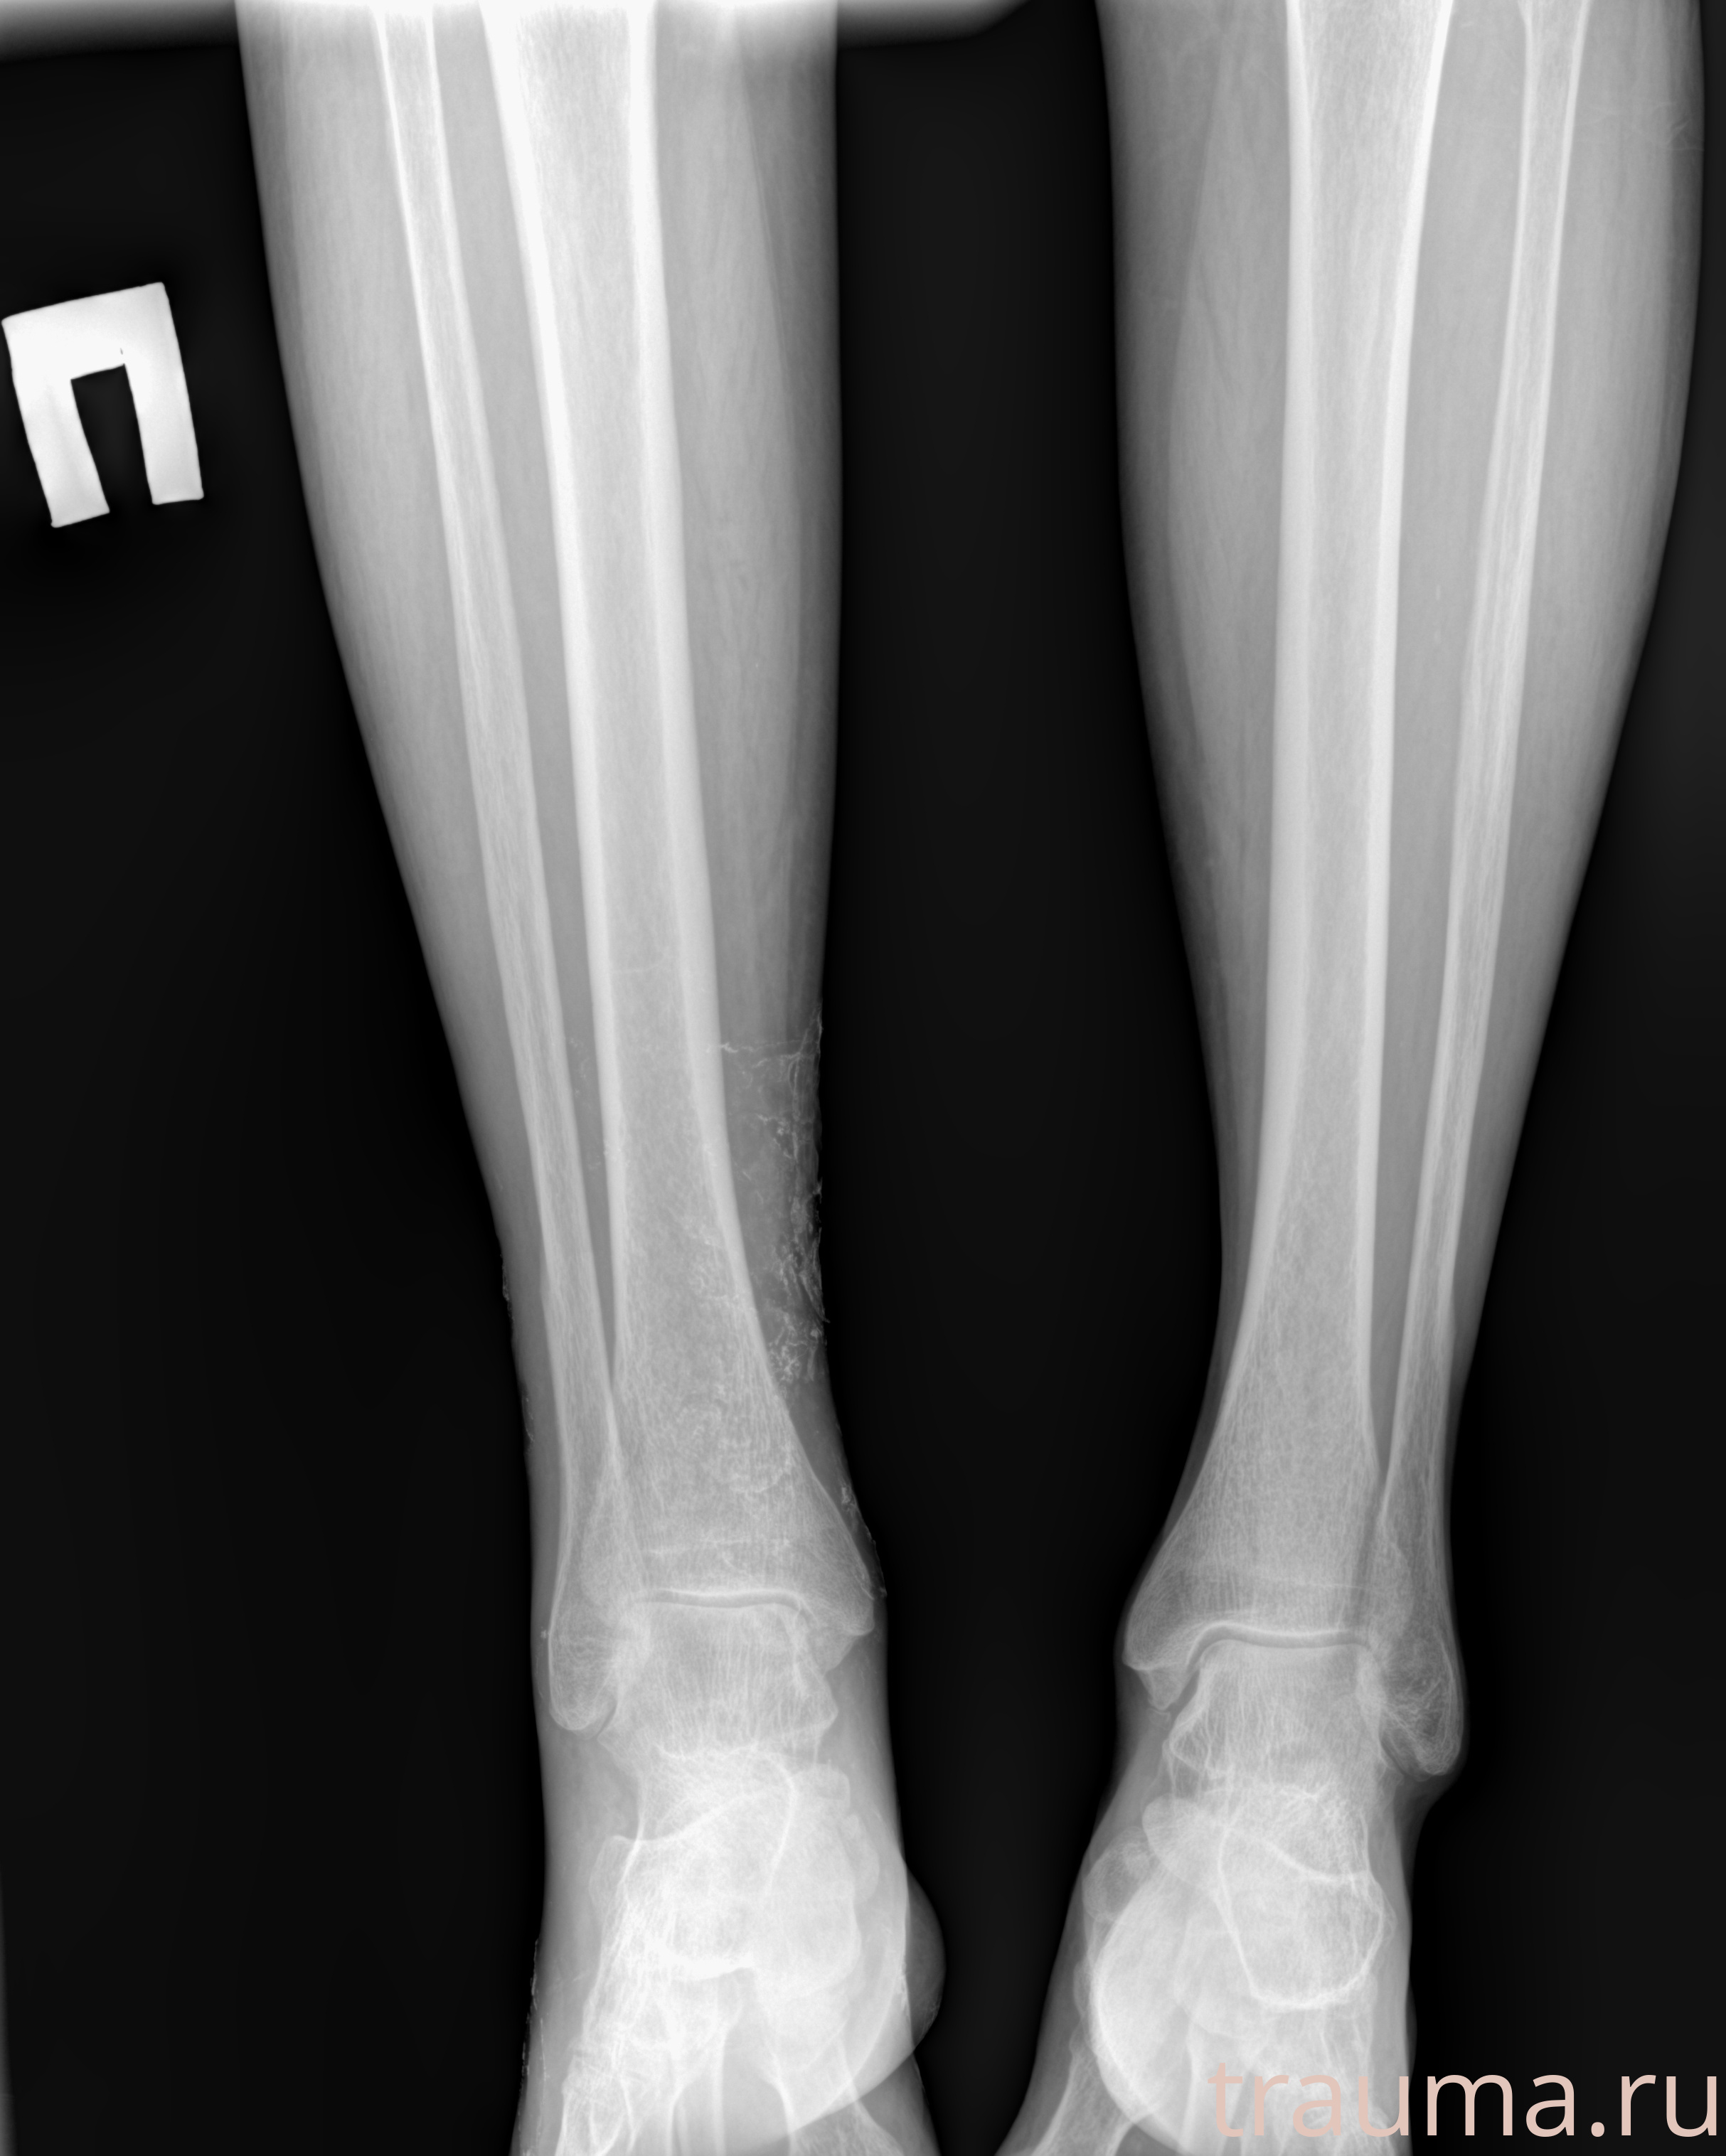

Рентген на дому: по вашему адресу приезжает врач-рентгенолог, травматолог-ортопед с мобильным рентгеновским аппаратом, проводит диагностику травмы или заболевания, делает необходимые рентгенограммы, дает рекомендации по дальнейшему лечению. Получить качественные снимки в домашних условиях возможно благодаря уникальной методике, разработанной МосРентген Центром для института  Склифосовского